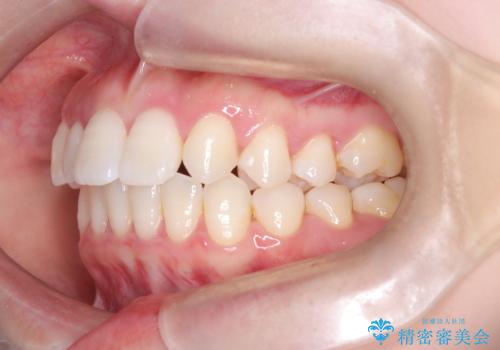

- 歯のデコボコと右上2番の歯の形が気になることを主訴に来院された患者様です。

軽度の叢生(凸凹)であったため、インビザラインのライトパッケージを用いて歯並びを改善しました。その後、右上2番はオールセラミッククラウンにより形態を回復し、審美性を向上させました。

歯並びと見た目がきれいになり、治療も短期間で終わったことから、患者様にも大変ご満足いただきました。